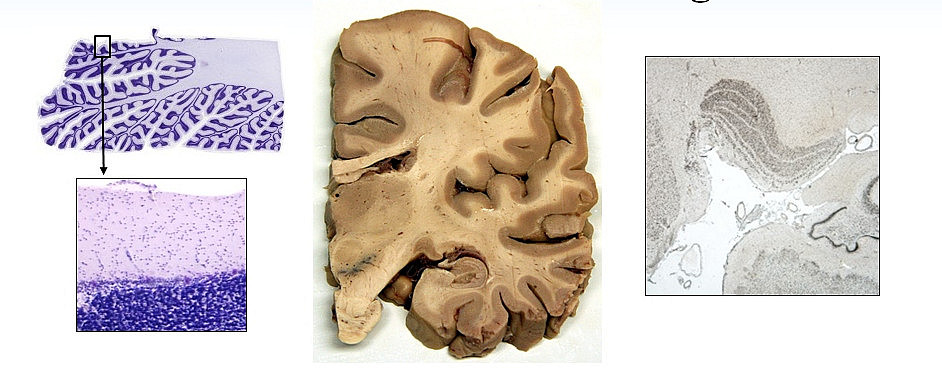

The aim of Module D is to provide an introduction into the structure and function of the human brain. The practical part, divided into microscopy and macroscopy, offers the possibility to get new insights on the cellular brain level and on the topographical anatomy of the human brain. The student groups are supervised by experienced scientists. Both, lectures and courses, contribute to the acquisition of a certain basic neuroanatomical knowledge.